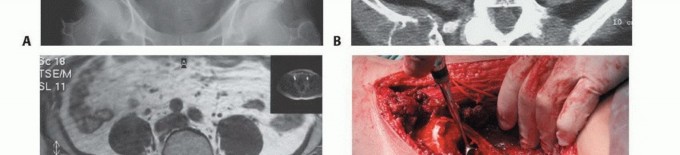

الفحوصات التصويرية المتقدمة:

- الأشعة السينية (X-rays): هي الفحص الأولي، ويمكن أن تكشف عن التغيرات العظمية مثل التآكل أو التصلب أو الكسور.

- التصوير المقطعي المحوسب (CT Scan): يوفر صورًا مقطعية مفصلة للعظام والأنسجة الرخوة، ويساعد في تحديد حجم الورم، مدى انتشاره داخل العظم، وعلاقته بالهياكل المحيطة.

- التصوير بالرنين المغناطيسي (MRI): يُعد الأداة الأكثر حساسية لتقييم الأنسجة الرخوة ونخاع العظم، ويكشف عن النقائل في مراحلها المبكرة، ويحدد مدى انتشار الورم في القناة الشوكية أو الأعصاب.